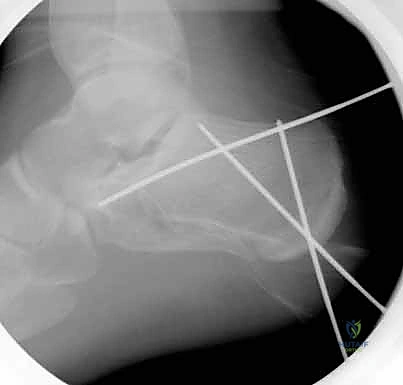

4. التثبيت المؤقت

يتم استخدام أسلاك معدنية دقيقة لتثبيت الشظايا في مكانها مؤقتاً، ثم يتم التحقق من دقة الرد باستخدام جهاز الأشعة السينية داخل غرفة العمليات (C-arm) لضمان عدم وجود أي انزياح ولو بمليمتر واحد.

5. التثبيت النهائي باستخدام الشرائح والمسامير (Plating)

يتم وضع شريحة تيتانيوم (Titanium Plate) مصممة خصيصاً لتطابق الشكل التشريحي لعظم الكعب. يتم تثبيت هذه الشريحة بمسامير قوية لتوفير ثبات ميكانيكي صلب يسمح بالالتئام السليم ويمنع انهيار العظم مرة أخرى. في بعض الحالات التي يوجد فيها فراغ عظمي كبير، قد يستخدم الدكتور هطيف طعوماً عظمية (Bone Grafts) لملء الفراغ.